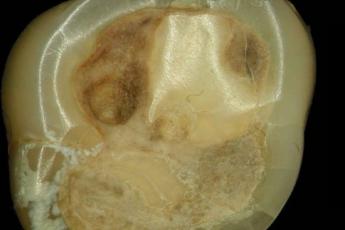

De opvallend gaaf gepolijste gaatjes zijn 1 tot 3 millimeter breed en maximaal 3,5 millimeter diep. De onderzoekers vonden ook vuurstenen boortjes. Ze experimenteerden met een nagemaakt exemplaar en konden daarmee inderdaad in korte tijd een gaatje boren in een kies. Ze lieten het stenen boortje draaien door er een touwtje omheen te slaan en dit heen en weer te trekken.